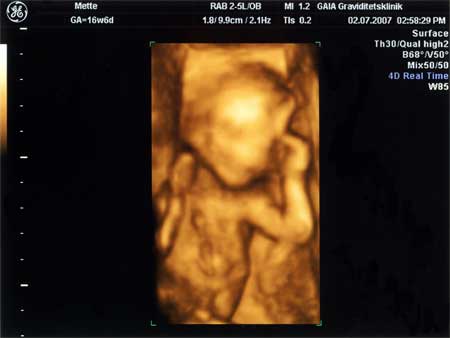

3D scanning – se baby i maven under graviditeten

3d scanning uge 16

3d scanning – uge 16

17 uge

Kønsscanning D. 23/04-2009. 16+4. Vi venter en lille perfekt Pige 🙂